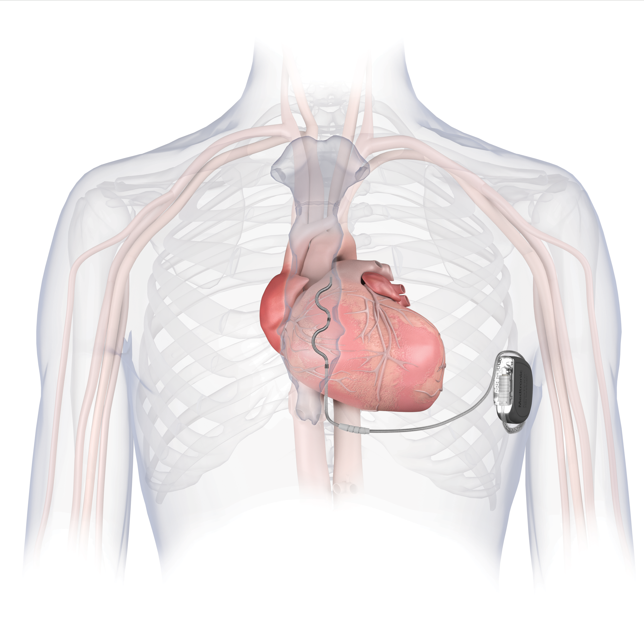

心脏性猝死是心血管疾病最常见的死亡原因之一,统计数据显示我国每年约有54.4万人发生心脏性猝死。心脏性猝死由于发病突然,病情极其凶险,大多发生在院外,抢救成功率极低,我国幸存者比例仅为1-2%。植入式心律转复除颤器(ICD)是预防心脏性猝死最有效的治疗措施。Aurora EV-ICD血管外植入式心律转复除颤器是全球首款可提供除颤复律和抗心动过速起搏治疗的血管外ICD,于2025年6月经国家药品监督管理局创新医疗器械特别审查程序(也称“绿色通道”)批准上市,是全球最新的植入式除颤系统。

Aurora EV-ICD 结合了现有经静脉和皮下ICD系统的优势,既不需要将电极植入心脏和血管内,同时实现了完整的除颤复律和抗心动过速起搏(ATP)治疗功能,装置体积小,预估使用寿命长达11.7年,为患者减少了未来设备更换的次数和经济负担。同时兼容1.5T 和3.0T MRI 全身磁共振扫描,术后更加美观舒适,不影响患者日常生活,是室性心律失常治疗及心脏性猝死防治领域的又一大技术突破。

我院心律失常专家乔青教授介绍:“Aurora EV-ICD™是国际上目前最新的植入式除颤器产品, 结合了现有经静脉和皮下ICD系统的优势,同时克服了传统经静脉植入式除颤器和皮下除颤器的缺点,为国内患者提供了全新心脏性猝死预防和治疗方案。此次EV-ICD首例临床应用标志着我院心脏性猝死防治技术更上一个台阶,让安徽省的患者能够与全球同步享受到创新医疗产品带来的临床获益。”(供稿:心脏大血管中心)